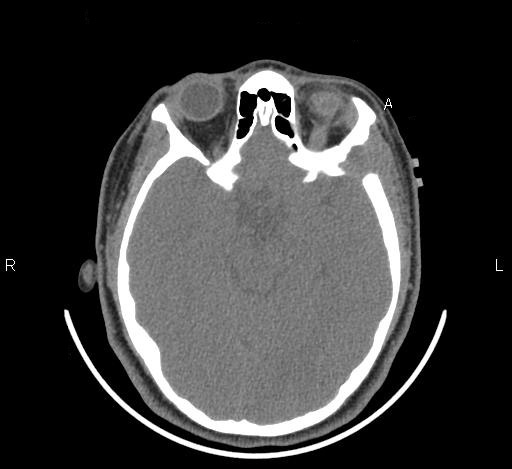

Clinical information: The patient was a 13 year-old girl who presented with worsening headache and some difficulties with memory, concentration and attention. MRI studies disclosed a 2.1 x 1.9 x 1.8 cm enhancing mass in the left temporal bone and sphenoid wing. The mass extended intracranially and abuts the left temporal bone accompanied by dural enhancement at that location. There is also extension through the bone into the submuscular temporal region. The following photos are taken from representative regions of the lesion. Panel 1 and 2 are CT scans at soft tissue and bone density respectively. Panel 3 and 4 are T1 weighed images without and with contrast respectively. Pandl 5 is proton density image. Panel A to D are cytologic (squash) prepartion for intra-operative consultation. Panel E and F are frozen sections for intraoperative consultation. Panel G to L are paraffin embedded sections.

The skin and bone are the most commonly affected organs but practically no organs are spared. The craniofacial bones and trunk bones are most commonly affected. The cranial base involvement may extend into the brain and involve the hypothalamus. The classic clinical triad of bony defects with exophthalmos and diabetes insipidus can be seen. The humerus and femur are less commonly involved. Small bones of the hands and feet are rarely affected. Radiologically, they occur as sharply demarcated, “punched out” osteolytic, usually intramedullary and rarely intracortical lesions. A thin sclerotic rim can be seen in some cases. Periosteal bone formation is usually not present. The lesion is usually small and about 1-2 cm in greatest dimension. Larger lesions may erode through the cortical bone and involve the adjacent non-osseous tissue as illustrated in this case.